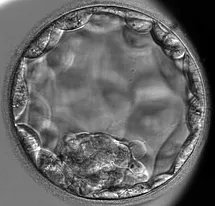

Our Cochrane review on growth factor supplemented culture media for IVF hot off the press! cochranelibrary.com/cdsr/doi/10.10… bottom line...GM-CSF supplemented culture media no more or less effective than standard culture media. @CindyFarquharNZ Allan Pacey MBE

Check out Cochrane's new special collection on the effectiveness of IVF add-ons. Really excited to see two of our reviews included as part of it. Cochrane Gynaecology & Fertility The University of Sheffield Sarah Lensen Bryan @CindyFarquharNZ #fertility cochranelibrary.com/collections/do…